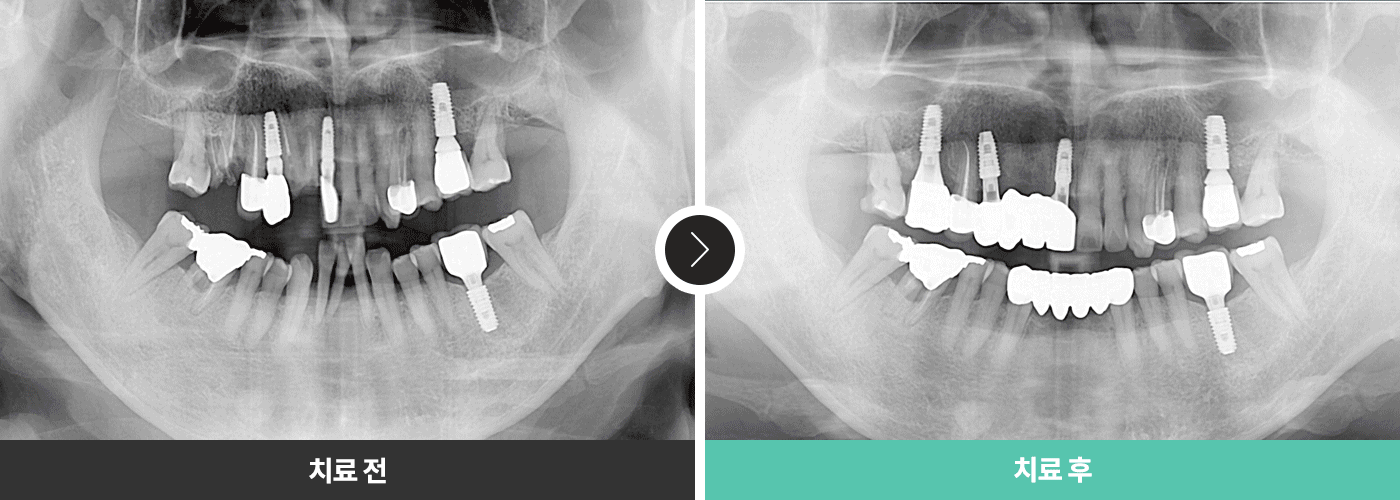

전후 사진

의료법에 의거하여 전후 사진은 로그인 후 확인이 가능합니다.